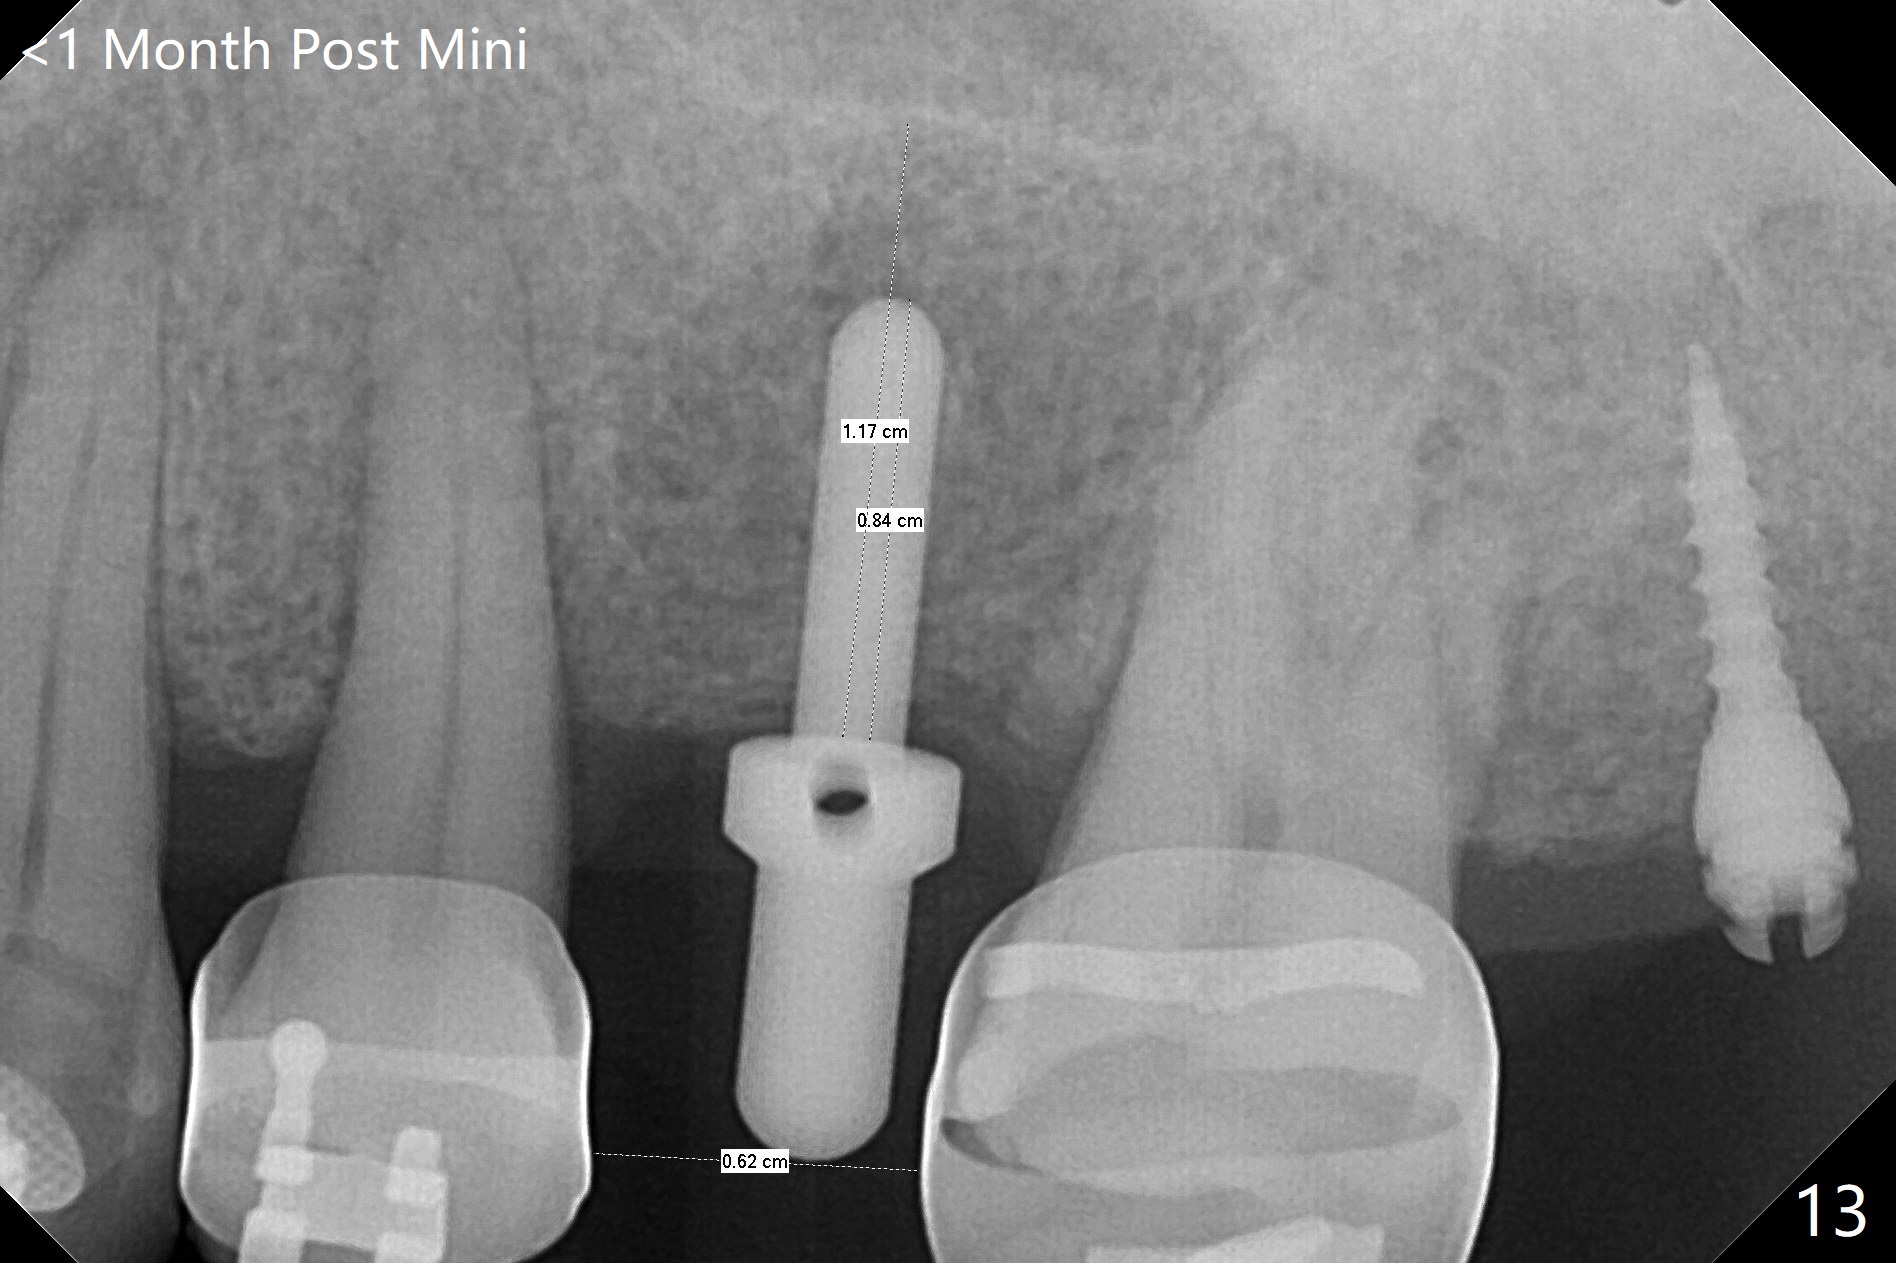

为了在左上6,左下7种植,使用右上3至左上5作为支抗推左上7远中,但是六个月效果不显著(图一),CT显示阻生牙(图一,二:8)没有阻挡。7远中植入1.6x8毫米微型植体,不过接近7根尖(图三),微型植体应该改变角度,而且往远中颊侧移位。最后效果不错(图四),植体马上启用(图五),而且同时取模做左下7导板。在微型植体牵引下,左上7的确往远中移位(图六,与图四对比),但是植体松动,马上植入3x10(2)毫米一段式植体,由于8阻挡,后者没有完全就位,稳定性差,没有启动。几天后也脱落。病人急着完成治疗,因为咀嚼困难。补救方法便是拔除阻生牙9(图七:x),让植体完全就位。切开后发现牙槽嵴处严重骨质吸收缺损(图八:D),离7很近,不适合种植。拔除8后(图九:S(socket)),两处植骨(粘性,图十),覆盖PRF膜,缝合。矫正九个月6空间相当双尖牙(图十二),还想增加2毫米才种植,病人急于完成治疗,所以再次植入微型植体,不同之处是切开,发现7远中颊侧骨质密度低(用探针),因此微型植体在腭侧植入(图十一:P),扭力似乎高,1.6x8毫米植体仿佛植入8牙槽窝(图十二:红虚线)。微型植体牵引一个月,磨牙缺牙间隙大约前磨牙大小,准备在远中(图十三)植入直径小植体(图十四),当后者整合时,用它继续推7。